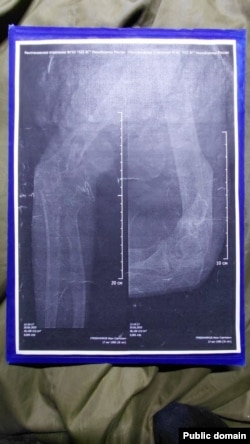

Здымкі зламанай рукі Івана Грабеньнікава

— Нам здавалася, што па вяртаньні з палону нас хаця б лячыць будуць. Куды там — нам нахабна памянялі катэгорыі на фальшывыя, мне, напрыклад, маю «Д» замянілі на «Б» (прыдатны да службы зь нязначнымі абмежаваньнямі), хоць у мяне правая рука як была ў некалькіх месцах перабітая — так і вісіць. У мяне дагэтуль куля ў целе — нават не апэравалі, — кажа Іван. — І нас такіх вельмі шмат — на мыліцах, у гіпсе. Ім проста п…й, вязуць на Данецкі кірунак калек.